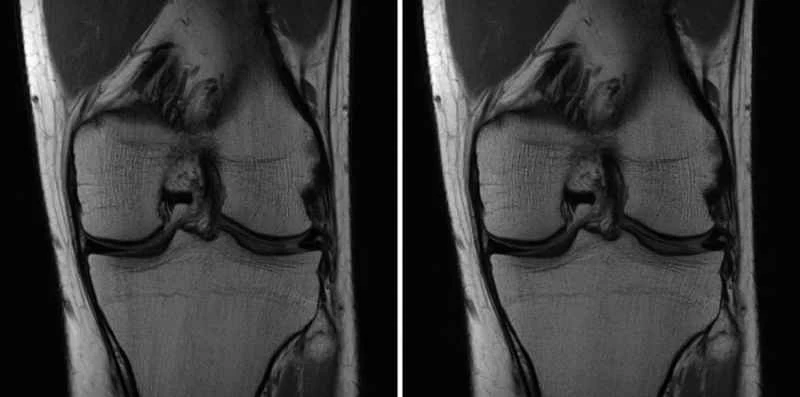

ジーナ・シアヴァラは、マンハッタンにあるニューヨーク大学ランゴン・ヘルスの暗い部屋に座っている。そこは読影室で、彼女のような放射線科医がX線やMRIのスキャン画像を検査する場所だ。目の前のモニターには、匿名化された患者の膝のグレースケール画像が映し出されており、彼女はそこに一つの重大な問題を発見した。前十字靭帯(ACL)断裂だ。「これは間違いなく異常です」とシアヴァラは説明する。

しかし、シアヴァラには、骨、靭帯、脂肪、軟骨、腱の渦巻きをスキャンして断裂や関節炎などの問題がないか確認するだけでなく、もう一つ評価しなければならないことがある。この膝のスキャン画像は人工知能(AI)によって作成されたものだろうか、それとも従来のMRI装置から生成されたものだろうか?「直感的にAIだと思います」と彼女は確信を持てずに言う。「ただ、少しぼやけているように見えるだけです」

シアバラ氏とニューヨーク大学の同僚たちは、AIが生成したスキャン画像と従来のスキャン画像の品質を比較した研究に参加しました。コンピューター科学者と放射線科医は、AIとMRI装置を組み合わせることで、一般的な医療検査を大幅にスピードアップできると考えています。これは患者と病院双方にとって大きなメリットです。例えば、10分かかる膝のスキャンを5分に、あるいは1時間かかる心臓スキャンを30分に短縮できる可能性があります。また、病院の費用削減や、じっとしていられない小児患者の麻酔の必要性軽減にもつながります。

放射線科医や外科医に必要な情報を提供し、この実験を成功と見なすためには、AI生成画像が2つの条件を満たしている必要があると、FAIRの研究科学者ラリー・ジトニック氏は説明する。まず、正確性が必要だ。靭帯の断裂を見逃したり、実際には存在しないものを偽造したりするような美しいスキャン画像は、役に立たないだけでなく、危険にもなり得る。次に、「放射線科医が画像を気に入る必要がある」とジトニック氏は言う。シアバラ医師のような医師が暗い読影室で何時間もスキャン画像を見つめるには、鮮明で目に優しい写真が必要だ。

Facebookはモデルを開発した後、鋭い観察眼を持つ専門家によるブラインドテストを実施する必要がありました。シアバラ氏をはじめとするニューヨーク大学の放射線科医たちは、AIによって生成された膝のスキャン画像と従来の方法で作成された膝のスキャン画像を検証し、両方から同じ診断情報が得られるかどうかを検証しました。そして、どちらが正しいかを推測する必要がありました。患者を2回スキャンする(つまり、より遅い通常の方法と、より高速なAIを活用した方法)のではなく、チームは通常のスキャン画像から生データの一部を遡及的に抽出し、機械をより高速に動作させた場合の状況をシミュレートしました。

ジトニック氏はまた、AIが生成した画像に少しノイズを加えてよりリアルに見せ、医師に情報が漏れるのを防いだと指摘する。「ちょうどいい具合に調整すると、放射線科医はどれがAIによるものでどれがそうでないかを見分けるのが非常に難しくなります。なぜなら、そこにあったたった一つのヒントが消えてしまうからです」と彼は言う。(追加されたノイズはスキャンの診断価値に影響を与えなかったと彼は言う。)